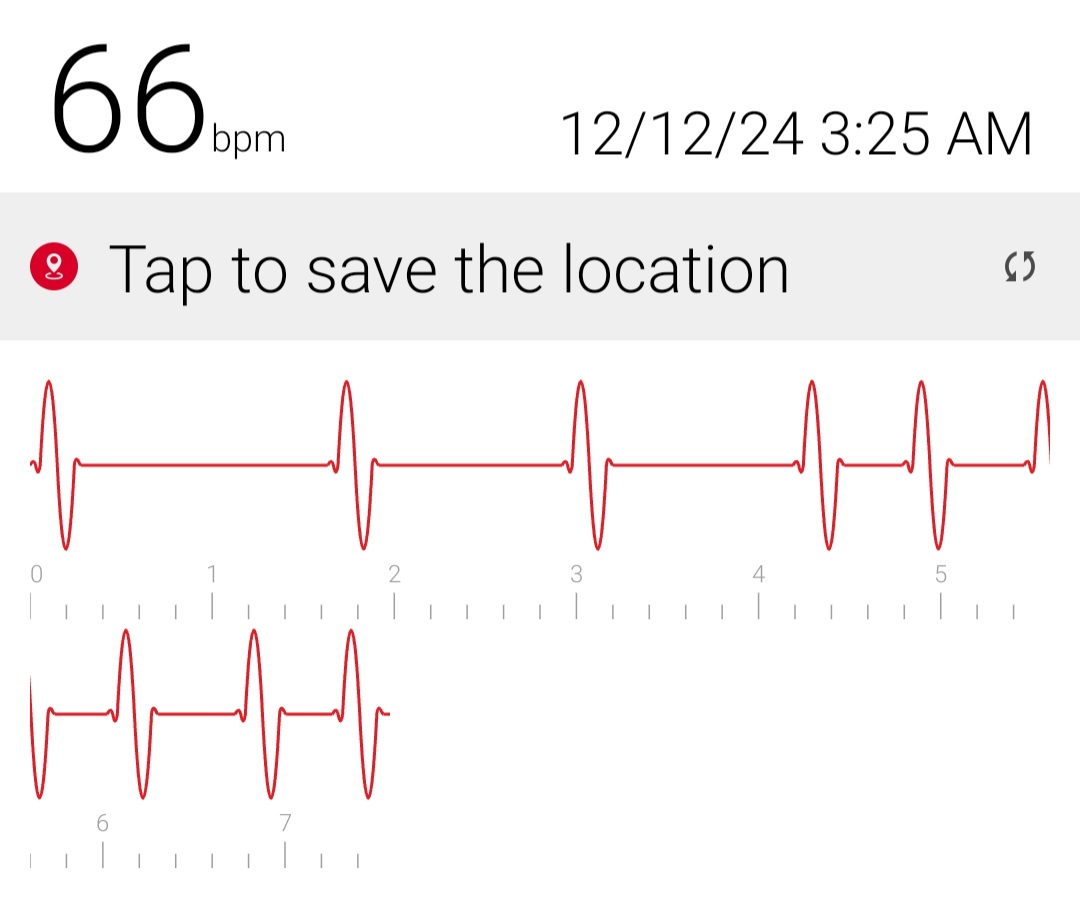

Initial ID consult diagnosed local tetanus based on clinical symptoms and recommended oral Metronidazole 500mg every 6 hours as an outpatient. Autonomic involvement developed with tachycardia and cardiac arrhythmia, along with episodes of sudden sweating. Loud noises made twitching/spasms worsen. Intermittent twitching continued to be present bilaterally in the body, face, jaw & tongue. Symptoms were suppressible with benzodiazepine. Tetanus IM IG 500 IU was recommended and obtained. After initial 2 week course of metronidazole was discontinued symptoms worsened again when patient would walk. Multiple trials of oral Metronidazole 500mg every 6 hours were attempted with some improvement while on the antibiotic but then return and worsening of symptoms again once antibiotic was discontinued.

incrementally, then once twitching had reached the spinal level, muscle twitching spread to the bilateral muscles of the body with cardiac arrhythmia & autonomic involvement/ sweating. A trial of antibiotic Keflex (cephalexin ) was suggested, which only at high dose (1000mg PO every 6 hours), helped keep spasms localized to the left foot mostly but symptoms would worsen and generalize if antibiotic Keflex (cephalexin) was stopped for more than 2 days. Benzodiazepine was increased to every q6 hours to reduce muscle twitching that had become constant in the left foot. Symptoms improve when patient does not walk or avoids any pressure or bending of left big toe and symptoms worsen when patient walks or stops antibiotic and has been unable to stop antibiotic for the past year and a half without worsening of symptoms. When antibiotic is stopped for 2 days bilateral jaws begin to snap shut intermittently involuntarily and cardiac arrhythmia/ heart block reoccurs. Symptoms worsen further after 4 days off antibiotic. Local

Oral Keflex (cephalexin) 1000mg 4 times a day & IM Bicillin LA 2.4 million units 3 times a week were restarted with improvement in bilateral body muscle twitching but twitching / spasms locally in the left toes and foot continued. This regimen was continued for 7 weeks. One day after discontinuing oral Keflex (cephalexin) (and 3 days after the last bicillin IM shot) spasms again began at the left big toe, left toes and left foot, progressed up the left leg to the left gluteal muscles and again once the spinal level was reached spasms spread to the right side of the body and then upper body and by 1 and 1/2 days after all antibiotic was discontinued, arrhythmia/heart block began again. Oral Keflex 1000mg 4 times a day was restarted (cephalexin). Benzodiazepines had been continued throughout.

3) Cardiac Arrhythmia / Heart Block occurs during generalizations

When antibiotic is discontinued or with increased walking, rhythm returns to normal when antibiotic is restarted after a few days.